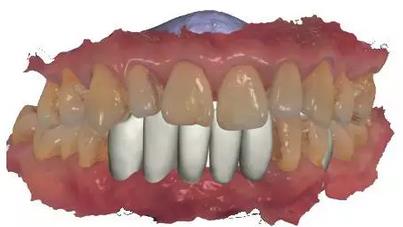

利用3shape導(dǎo)板軟件虛擬排牙

以修復(fù)為導(dǎo)向規(guī)劃植體

通過(guò)3Shape Dental System軟件同期設(shè)計(jì)臨時(shí)冠